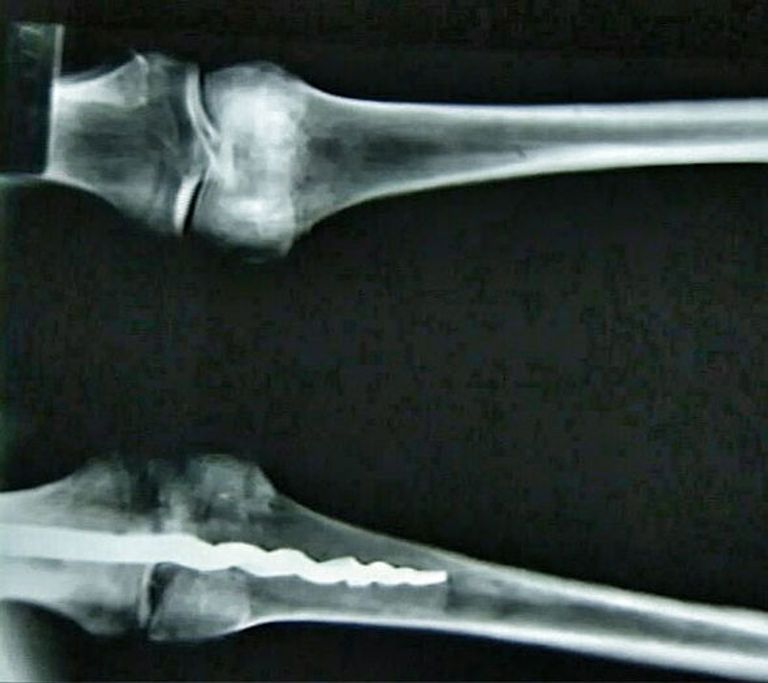

حالة "المسمار" الذي يعود إلى 3500 عام كانت ممتازة ولا يختلف تصميمه كثيرا عن التصميمات الحديثة.

وأضاف لـ"العين الإخبارية"، أنه أثناء فحص المومياء التي تعود إلى 3500 عام وجد الباحثون مسمارا معدنيا بطول 23 سم تم تثبيته في عظام الركبة باستخدام مادة "الراتنج العضوية"، لربطها بعظام الساق بدقة بدت مذهلة.

وأشار عبدالعليم إلى أن الشيء الذي كان ملفتا للباحثين هو أن حالة "المسمار" الذي يعود إلى 3500 عام كانت ممتازة، ولا يختلف تصميمه كثيرا عن التصميمات الحديثة.